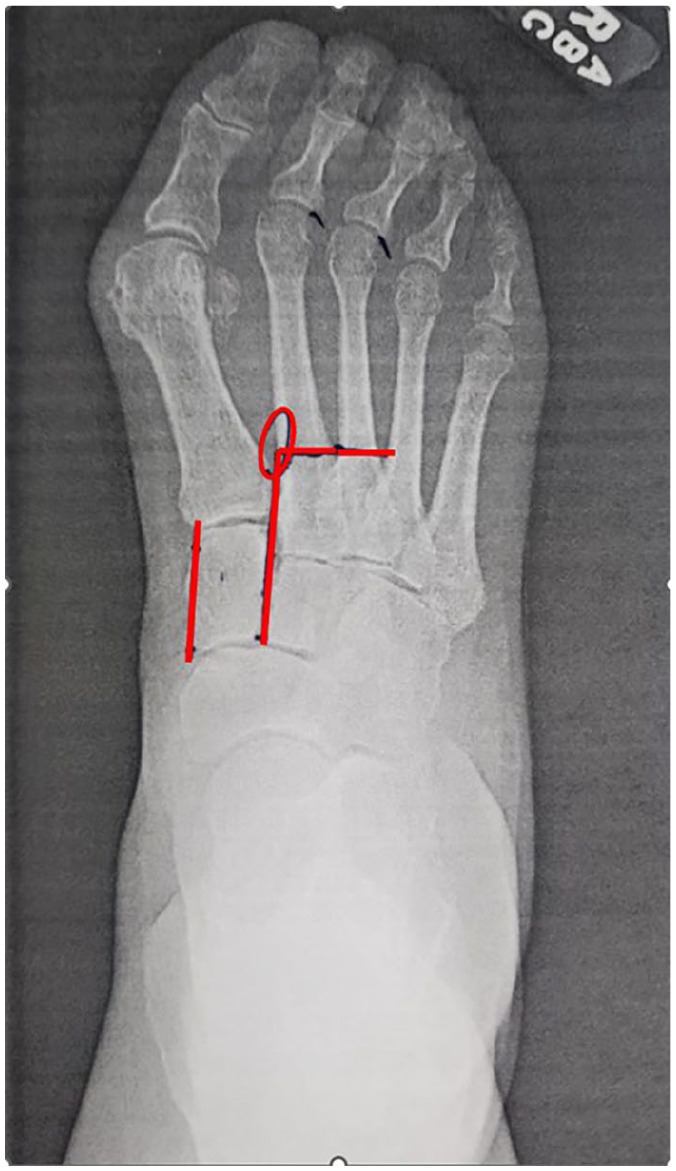

Approaches to Minimally Invasive Surgery for Treatment of Metatarsus Adductus with Hallux Valgus Correction With Modified Lapidus: A Novel Technique Guide.